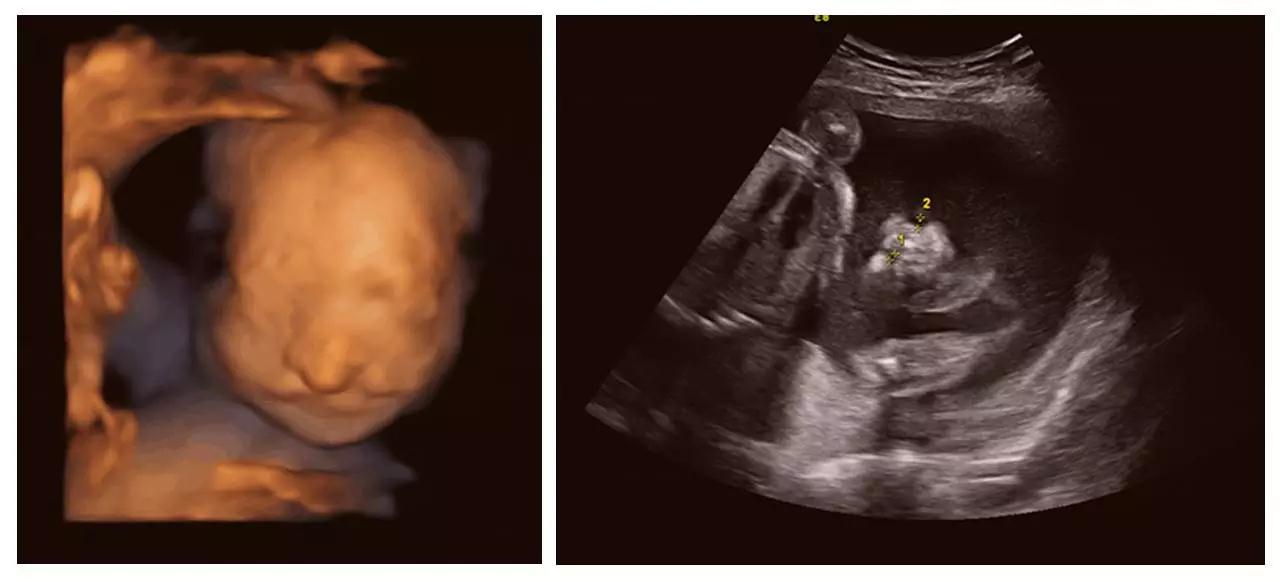

正是通过神奇的四维彩超(四维彩超),我们一起见证了这有爱的一幕。四维彩超(四维彩超)的出现对于妇产科学界意义重大,在探头下,我们可以清晰地看见宝宝的动态,看见宝宝发育的情况。不仅如此,四维彩超(四维彩超)能通过清晰的画面对胎儿的体表进行检查,及早发现唇裂、脊柱裂,大脑、肾、心脏、骨骼发育不良等各种畸形情况,检测和发现各种异常。简单的说,四维彩超(四维彩超)的作用,就是从零岁起监测宝宝的发育情况,保障每一个新生儿的健康!

济南艾玛妇产医院作为山东首家 JCI 金牌妇产专科医院,在今年年初,又顺利成为济南市基本医疗保险定点医疗单位,集医疗安全和客户就诊的便捷度于一体。济南艾玛妇产医院一直非常重视围产期保健及宝宝出生缺陷的预防,率先引进美国GE-E8高清四维彩超(四维彩超)设备,从0岁开始守护宝宝的健康,见证宝宝的成长。

艾玛妇产成功筛查胎儿畸形的案例(部分)——

(单侧唇裂)

(双侧唇裂)